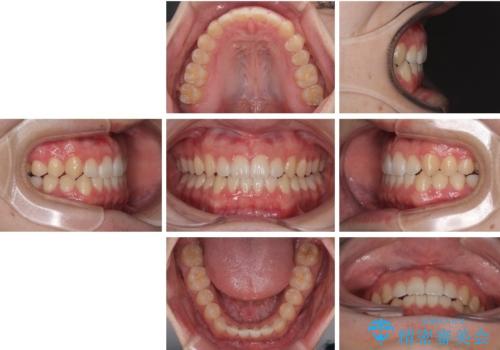

患者様は「できるだけ目立たない矯正治療」を希望されていたため、インビザラインを用いた治療計画を立案しました。

インビザラインは透明で装着していても気づかれにくく、日常生活やお仕事への影響を最小限に抑えながら治療を進めることが可能です。

そこで矯正治療と並行して**MFT(口腔筋機能療法)**を実施し、舌や口周囲筋の正しい使い方を習得していただきました。

マウスピース矯正特有の奥歯への圧下により、一時的に噛みにくさを感じる場面もありましたが、

装着時間の調整と経過観察を行うことで症状は改善し、スムーズに治療を完了しました。